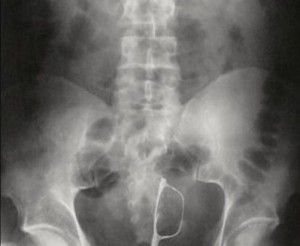

ბილიარდის ბურთი

10 (1)